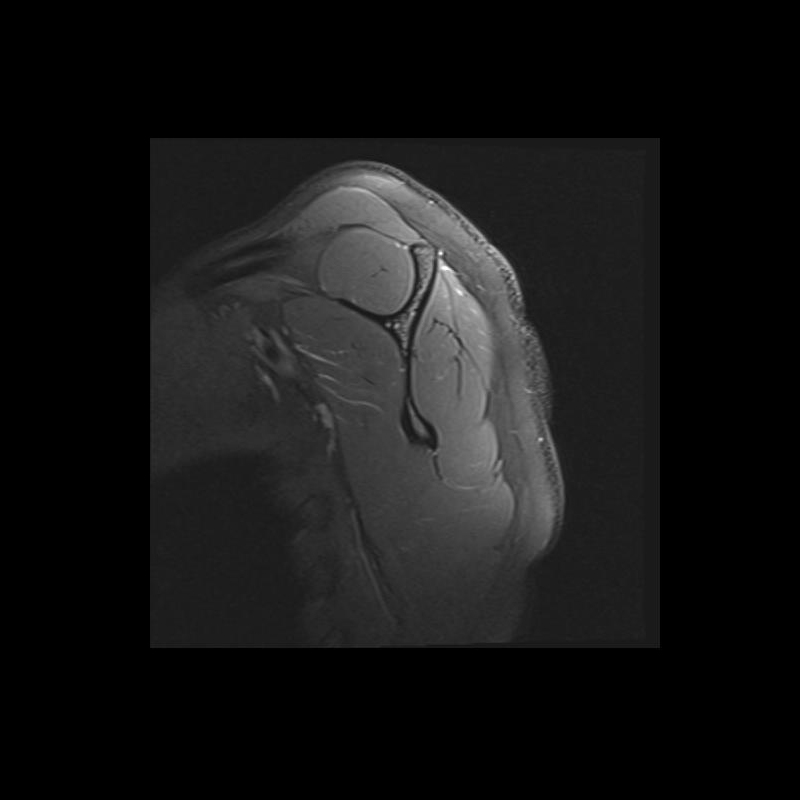

Shoulder MRI Anatomy